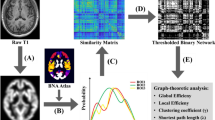

Comparison of functional connectivity in the region of interest

The one-sample t test of sFC and dFC showed that the bilateral posterior hippocampus and anterior hippocampus with high sFC and dFC values were mainly connected to the bilateral frontal cortex, temporal cortex, and parietal cortex. The bilateral anterior hippocampus with high dFC and sFC values was mainly connected to the bilateral frontal cortex, temporal lobe, occipital cortex, parietal cortex, and limbic cortex (Fig. 1). The spatial distributions of dFC and sFC values in the SCD group were similar to those in the HC group.

The one-sample t test of functional connectivity patterns of the bilateral anterior and posterior hippocampus in the SCD and HC groups. The one-sample t test of sFC and dFC showed that the bilateral posterior hippocampus and anterior hippocampus with high sFC and dFC values were mainly connected to the bilateral frontal cortex, temporal cortex, and parietal cortex. The bilateral anterior hippocampus with high dFC and sFC values was mainly connected to the bilateral frontal cortex, temporal lobe, occipital cortex, parietal cortex and limbic cortex. LAHP, left anterior hippocampus; LPHP, left posterior hippocampus; RAHP, right anterior hippocampus; RPHP, right posterior hippocampus; HC, healthy controls; SCD, subjective cognitive decline; sFC, static functional connectivity; dFC, dynamic functional connectivity